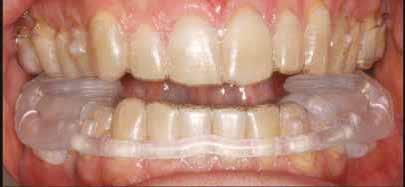

Az Essix retainerek, az egy fogívre kiterjedő mélyhúzott sínek, valamint a felső és alsó frontfogakra orálisan ragasztott fix retainerek mellett, a harapás sagittális rögzítésében elengedhetetlen szerepe van az ún. Pitts Izom Tréning Splint-nek, amelybe a páciens élharapásban összeharap, így az megakadályozza az alsó fogsor visszamozdulását a disztálharapásos helyzetbe (13. kép)